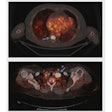

New PET tracer detects lung tumors

December 3, 2021